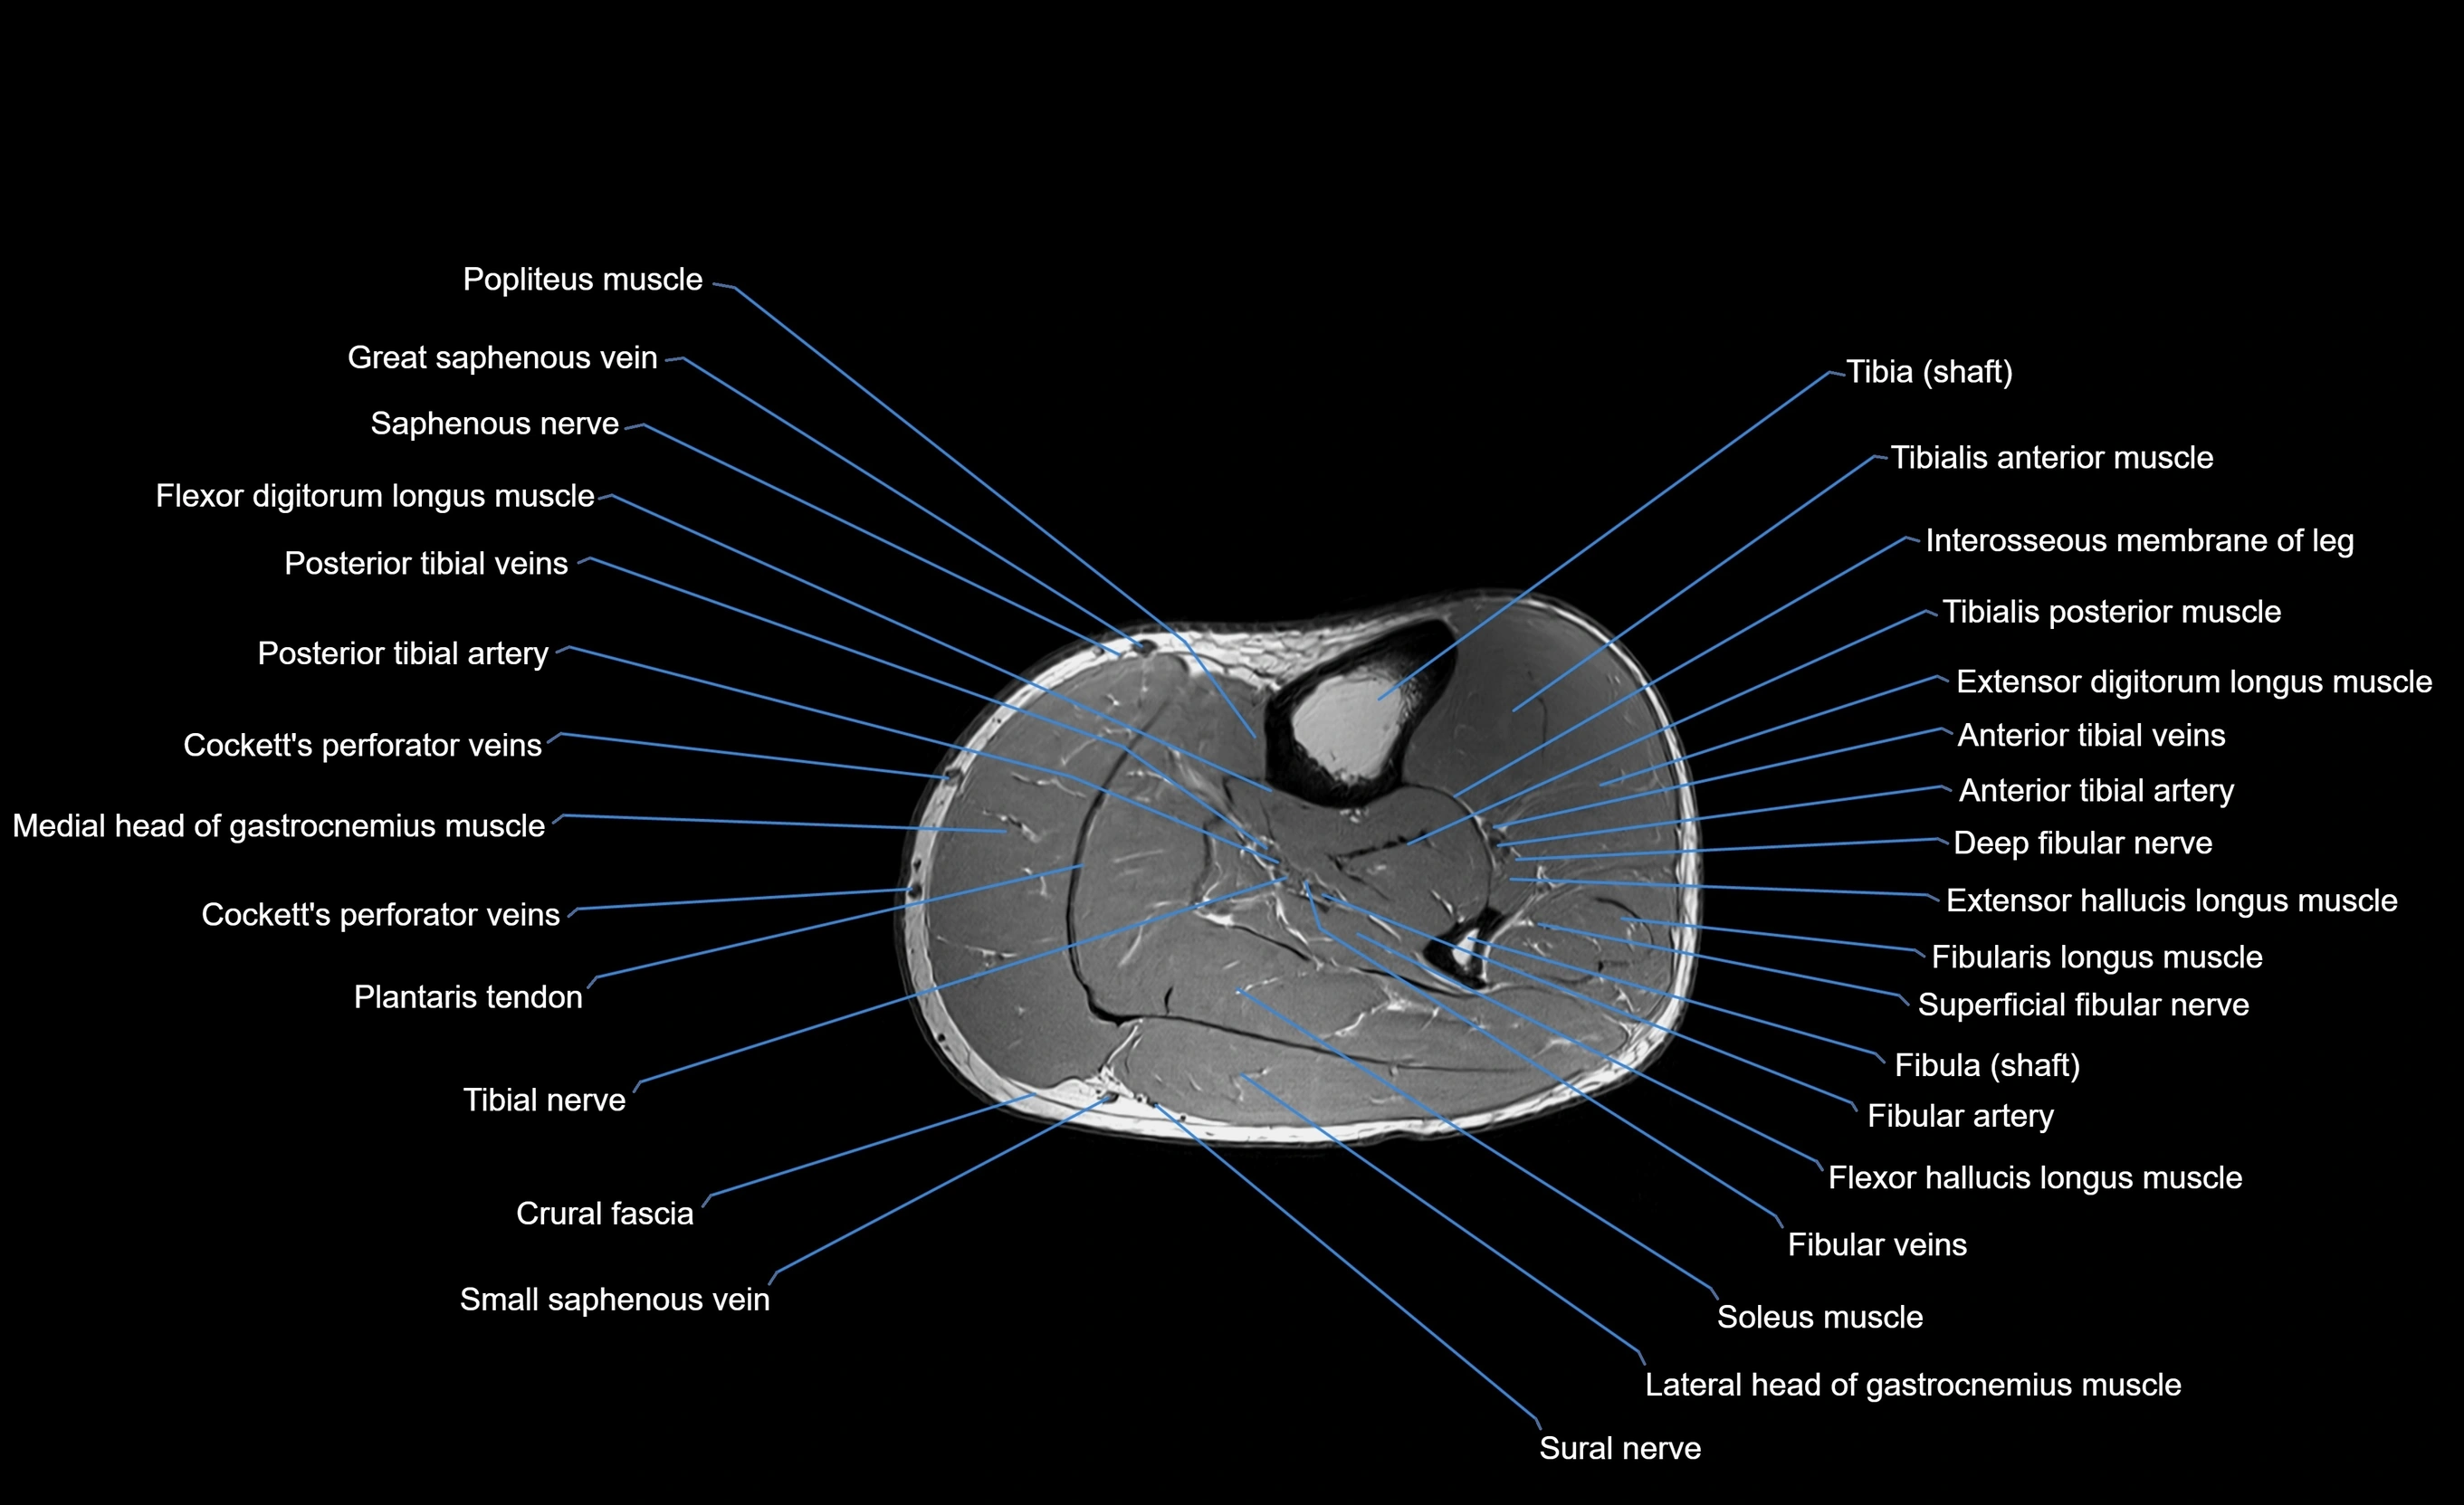

MRI image